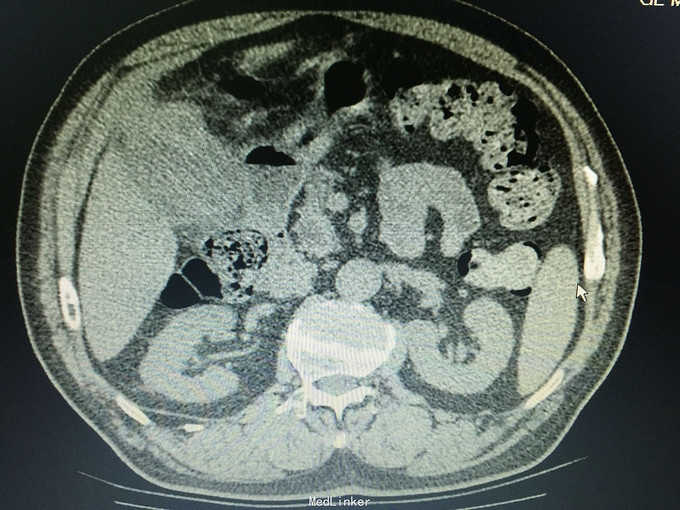

男,74岁 主诉:反复右上腹疼痛10年,再发并加重一天, 现病史:10年前开始反复右上腹疼痛,持续性绞痛,向同侧肩背部放散,曾经在当地医院以“胆囊结石”治疗,效果不佳,10年来反复发作,10小时前再次发作并疼痛难忍,来诊,无发热,无恶心、呕吐,尿色深,大便正常。

痛苦表情,皮肤及巩膜轻度黄染,腹部平坦,右上腹压痛,无肌紧张及反跳痛,未及包块,莫氏症阳性,肝区扣痛明显。 辅助检查:CT:胆囊轮廓欠清晰,密度不均,底部局限性增厚并向内突起,胆囊内见高密度影,胆总管扩张。

诊断:胆囊占位,胆囊结石,胆囊炎 处理:手术治疗,术中见大网膜与腹膜广泛粘连,胆囊质硬,与肝脏、12指肠及横结肠广泛粘连,与胃小弯及幽门部侵润致密。行胆囊癌根治术,胃破裂修补术,胆总管切开T形管引流,腹腔冲洗引流术。病理证实为胆囊中分化腺癌侵及浆膜层。(胆囊及胆总管内未见结石)